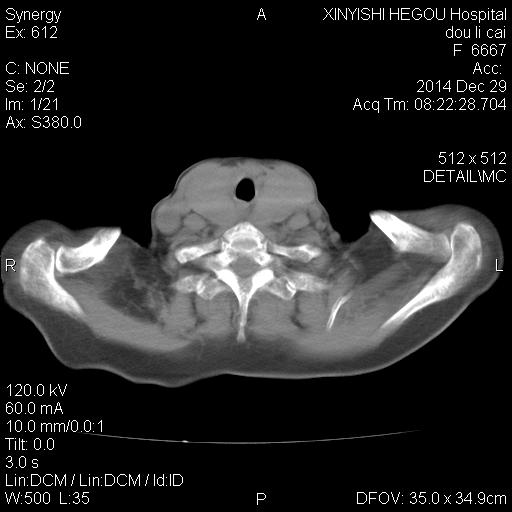

CT49652:女,71岁。

胸闷一周

考虑双侧甲状腺肿